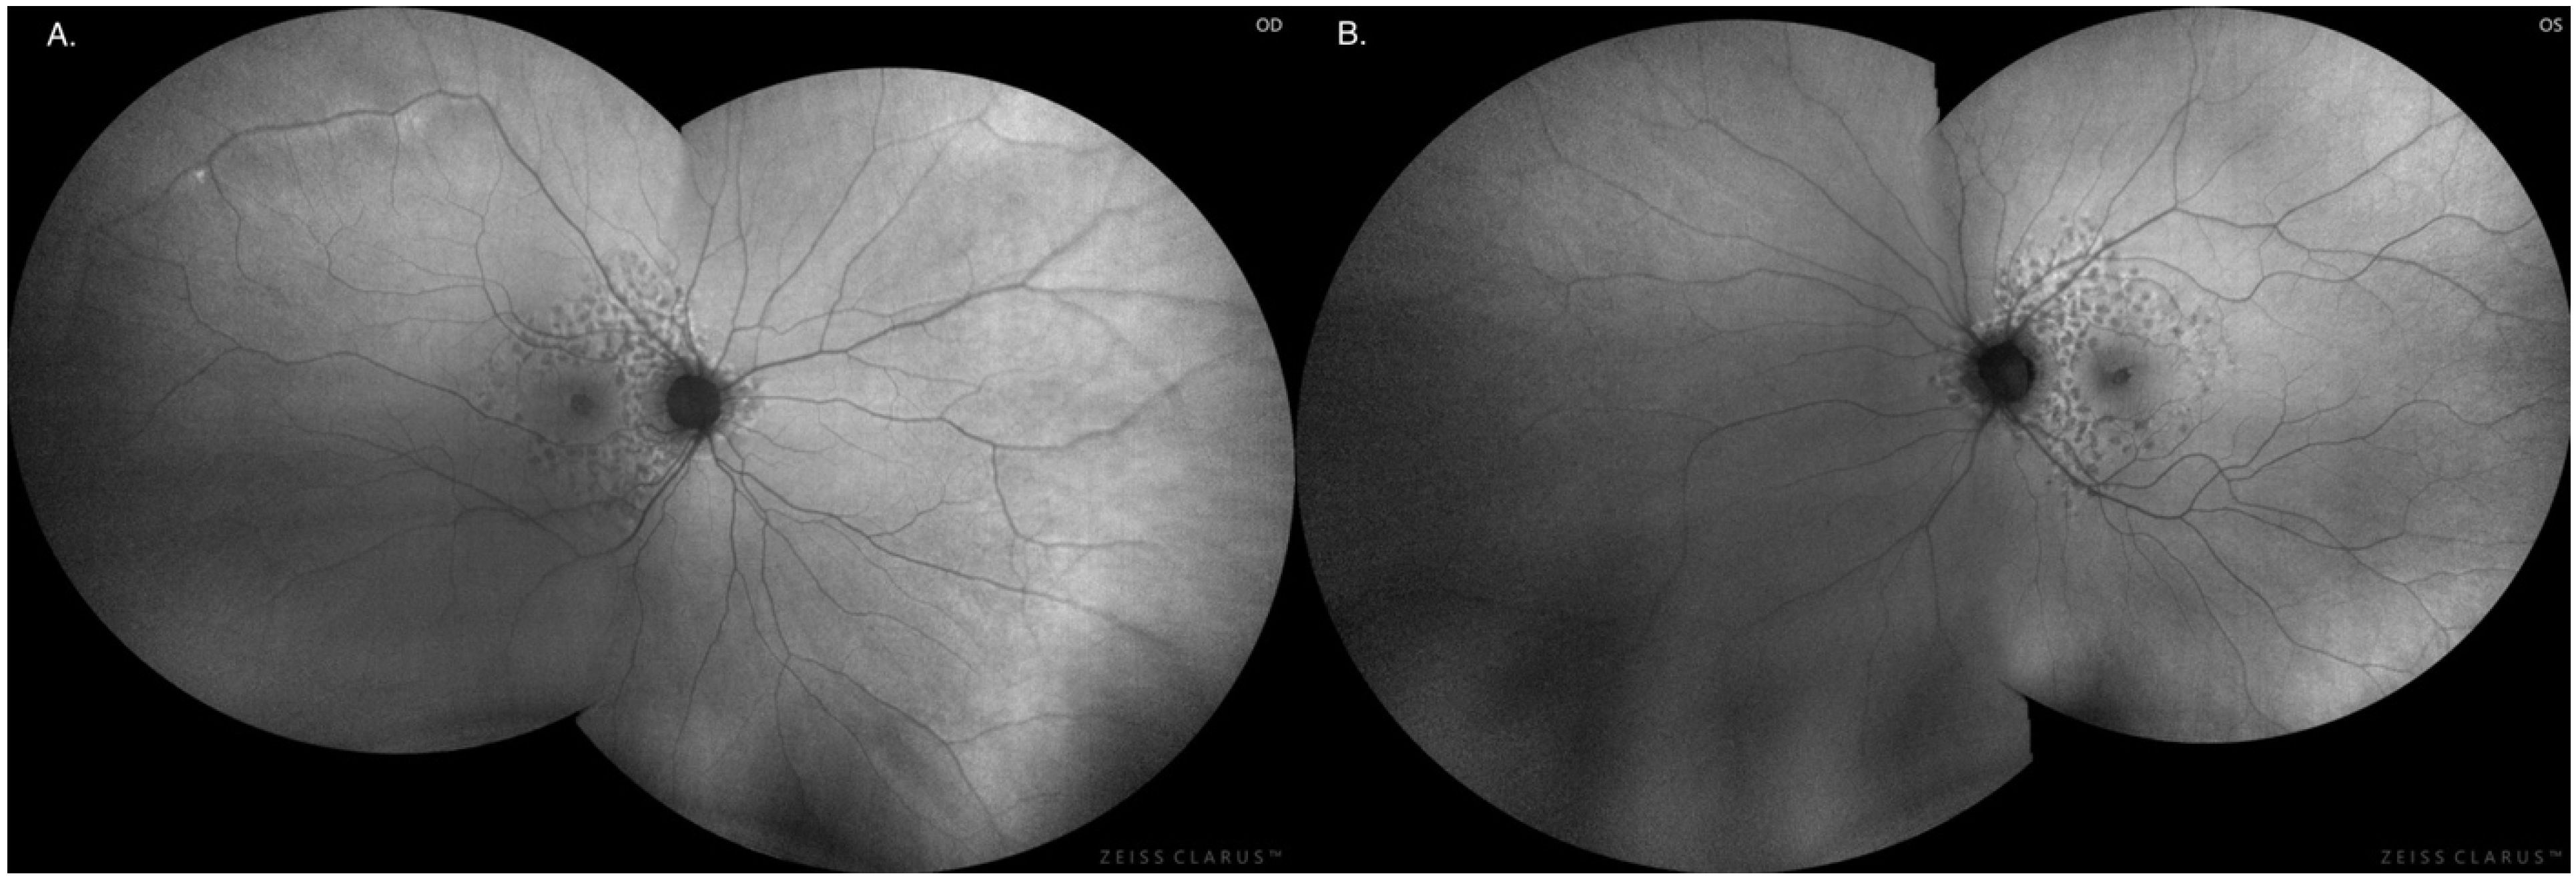

Figure 3. Fundus imaging in the right eye (A) and left eye (B), respectively.

No abnormalities were found during the examination of the anterior segment of the eye, intraocular pressure, Ishihara test for color vision or Farnsworth D-15 color test. Intraocular pressure in both eyes was normal: 16.5 mmHg for the RE and 17.2 mmHg for the LE (ICARE tonometer). In the eye fundus, indirect ophthalmoscopy by a Volk lens revealed symmetrical bilateral lesions with a characteristic pattern in the form of a circular rearrangement of RPE cells around the optic disc (foci size approx. one disc diameter) and hypertrophic hyperpigmentation around the macula extending to the periphery of the retina, forming a characteristic reticular pattern (resembling a fishing net) towards the perimeter (zones 2, 3). The retinal vessels were normal. There were no structural anomalies of the retina in macular OCT: central retinal thickness RE 282 μm and LE 279 μm. No anomalies in kinetic perimetry and no deficiencies in color perception were noted in color vision tests (Ishihara test and Farnsworth D-15 test) [Figure 2].

The degenerative lesions in the retina in the form of hyperpigmentation of RPE cells and their characteristic image and location at the fundus of both eyes were confirmed by autofluorescence imaging as numerous patchy or mosaic foci of hypofluorescence [Figure 3 and Figure 4].

Reticular pattern of pigment epithelial hyperpigmentation morphologically like a fishing net with knots.